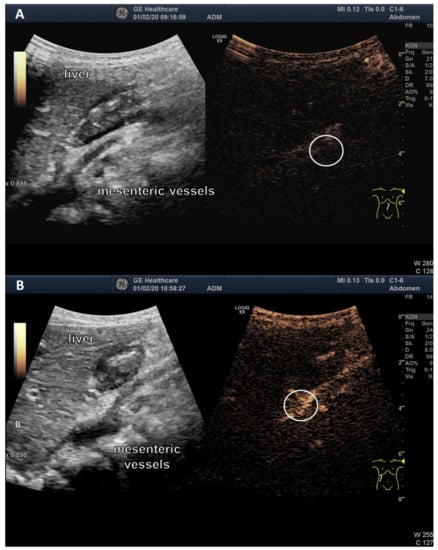

3.3. Ultrasound Examination of Intestinal Absorption